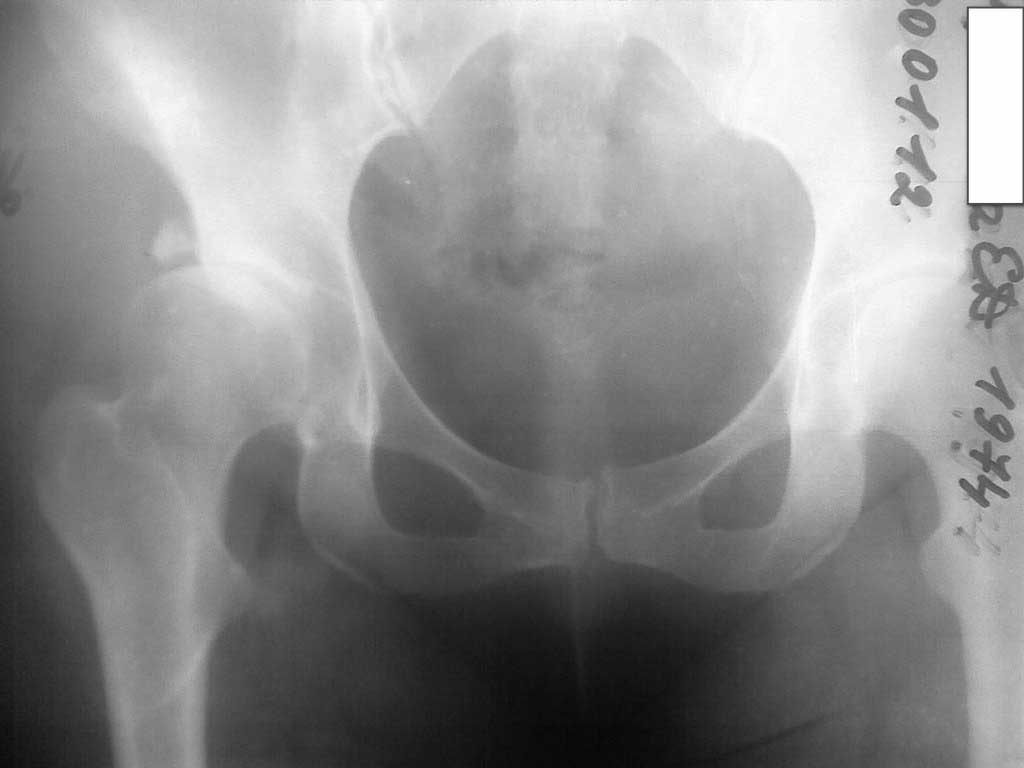

Добавляю снимков для "информационной поддержки принятия решения" (ну, нравится мне это выражение )). Поступило предложение выполнить артроскопию для оценки сохранности хряща. Насколько это необходимо?